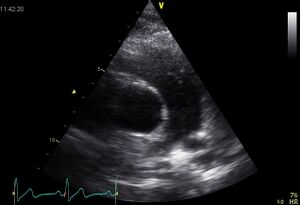

| Plax by tilted (Plax PV) | PSax Ao |

| Suprasternal apd (color doppler) | Dilated apd (Plax PV) |